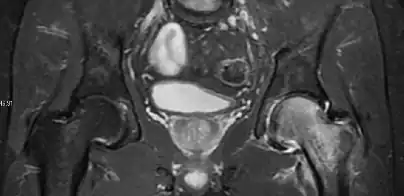

Magnetic resonance imaging

Many pathological conditions of the hip are detected early by MRI due to its high soft tissue resolution and sensitivity. Its accuracy in studying acute hip pain in children has proved to be superior to ultrasound and plan film radiography. However, MRI accessibility and the need of sedation relegate its use to selected cases in which diagnosis is not clear with less demanding techniques. These include differentiating transient synovitis from a septic arthritis or osteomyelitis, diagnosis of inflammatory joint disease or bone tumors, and early detection and follow-up of Perthes disease.[1]

In adults, MRI is currently playing a definite role in the assessment of osteoarthritis. Although traditionally belonging to the arena of radiographs, the role of MRI has been stressed after the term femoral acetabular impingement was coined in 2003. Growing interest has been focused in accurate diagnosis of the acetabular and femoral morphological abnormalities that may lead to early osteoarthritis.[1]

MR imaging is considered paramount to these objectives, mainly when surgery is considered, due to the ability of MRI to portray the whole section of the femoral neck surface, as well as to image the labrum and articular cartilage.[1]

Diagnosis of impingement can only be achieved if, besides imaging findings, there are also clinical symptoms and positive impingement maneuvers.[1]

Most of the angles and measurements described in the plain radiograph section can be accurately reproduced on MRI. In addition, the superiority of MRI resolution with intra-articular contrast allows detection of labral and chondral abnormalities that may influence the choice of medical, percutaneous, or surgical management (Figure 9).[1]